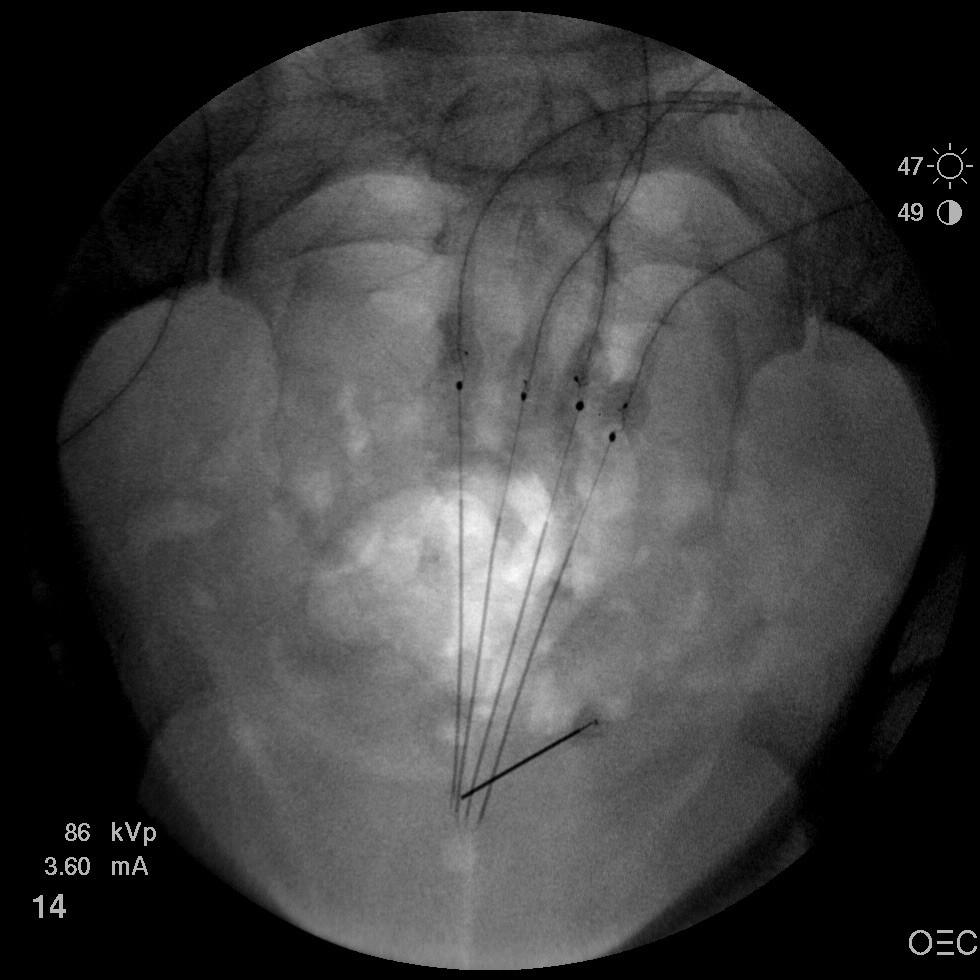

I have a patient with several months of coccyx pain. Worse with sitting, TTP over coccyx. Otherwise normal exam. No trauma, but she has an anteriorly displaced coccyx. Failed NSAIDs and no one around me does good pelvic floor PT. I scheduled her for ganglion impar injection, but her insurance won't pay for it. They wouldn't even let me to a peer-to-peer... they just straight up said they won't cover it. Any other treatment options? I don't want to send her to a surgeon. Thanks.